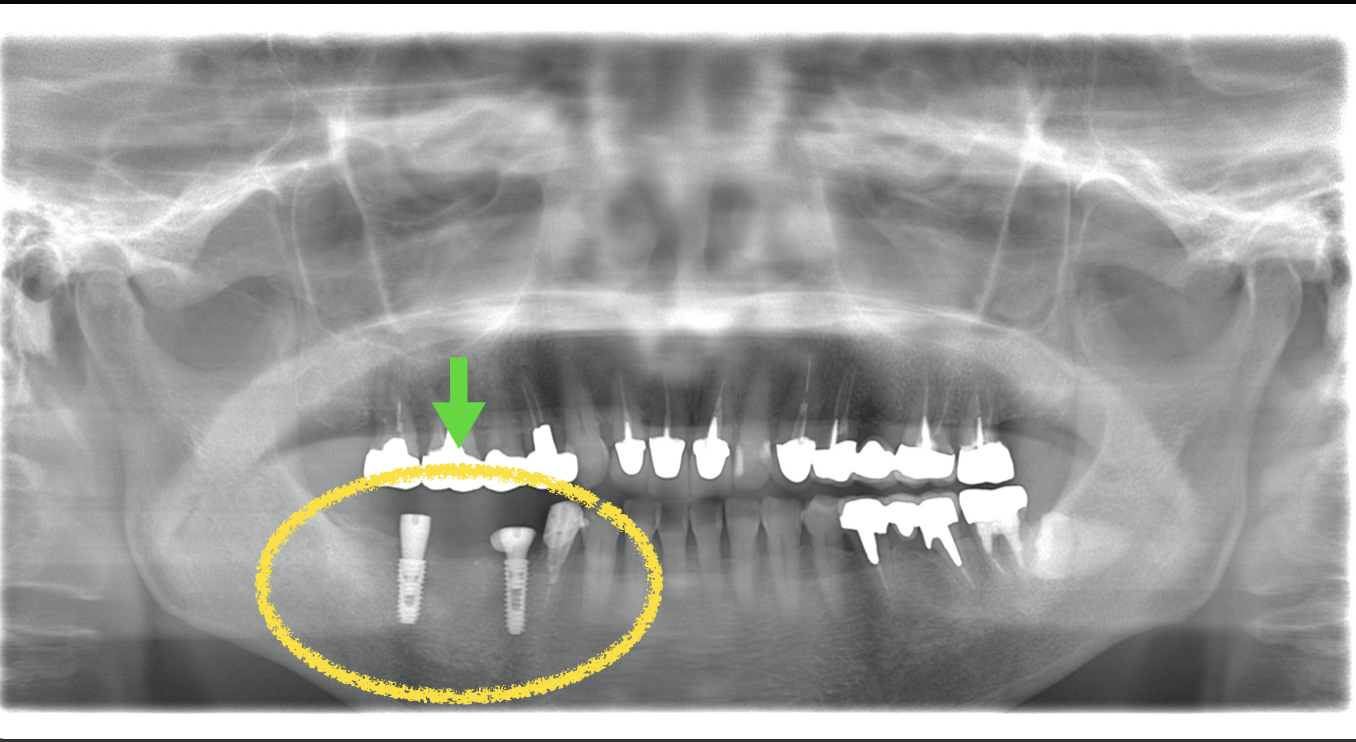

1番右の画像が手術後2ヶ月のものです。インプラントの周りの隙間は無くなっており、うまく治癒できたのが確認できます。

黄色の枠の中の白いものがジルコニアブリッジです。綺麗に入りました。

このケースでは手術後約4ヶ月でインプラント部に歯が入りました。黄色い枠線で囲ってある3本の歯がインプラントの歯です(ジルコニア)。

もしインプラント即時埋入でなく通常の待時埋入をしてたらさらに+6ヶ月かかっています。